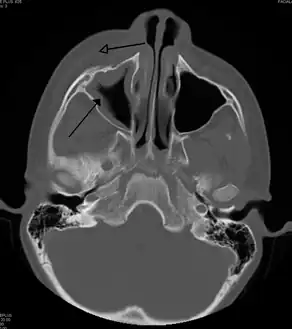

Periorbital cellulitis caused by a dental infection (also causing maxillary sinusitis)

Periorbital cellulitis, or preseptal cellulitis, is an inflammation and infection of the eyelid and portions of skin around the eye anterior to the orbital septum.[1] It may be caused by breaks in the skin around the eye, and subsequent spread to the eyelid; infection of the sinuses around the nose (sinusitis); or from spread of an infection elsewhere through the blood.

Tests include blood work (CBC) to rule out infectious cause. Also perform a CT scan, x ray of the anterior skull to view the sinuses, MRI scan and finally a soft tissue ultrasound of the orbital region.